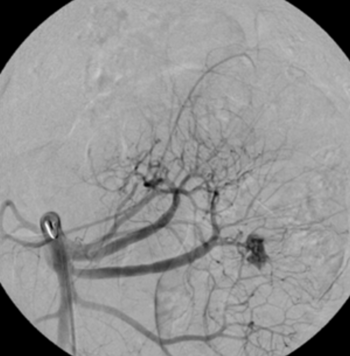

Digitale Subtraktionsangiografie: Superselektive Sondierung und Darstellung der mutliplen Blutungsherde. Die Leberarterien werden durch die zystischen Metastasen ausgespannt.

Digitale Subtraktionsangiografie: Nach Spiralembolisation mehrerer Subsegmentäste der A. hepatica stehen die zahlreichen Blutungen.